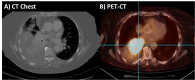

Figure 1. A) Chest computed tomography (CT) scan demonstrating right lower lobe consolidation with moderate to large sized right pleural effusion and B) positron emission tomography-computed tomography (PET-CT) scan demonstrating increased fluorodeoxyglucose (FDG) uptake in the heterogeneous right lower lobe pulmonary mass involving bronchus intermedius and right lower lobe bronchus